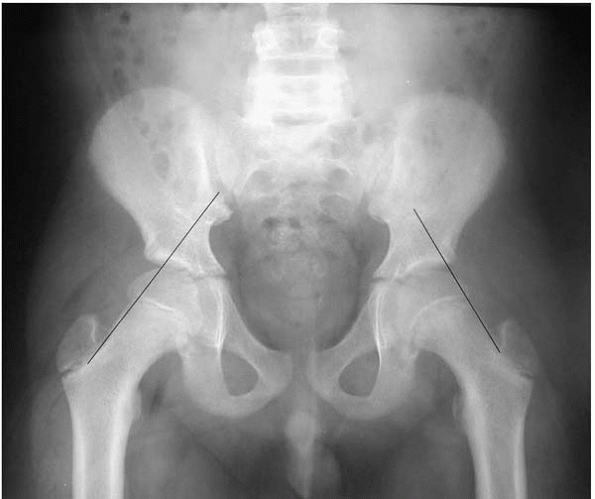

a source of trouble with SCFE. An AP and frog lateral of both hips

widening, a break in Klein’s line (Fig. 22-7) or a decrease in femoral epiphyseal height of the involved side compared to the opposite side.

▪ FIGURE 22-7

Using Klein’s line will help keep you out of trouble. The line drawn along the superior neck on the AP radiograph intersects less epiphysis on the left (SCFE) side.  |